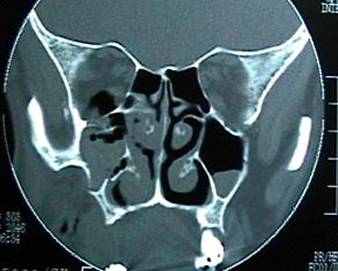

Orbital fractures 1

Baseline fracture involving the left orbit